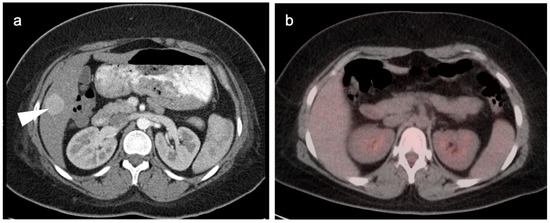

7. Adrenal Cancer